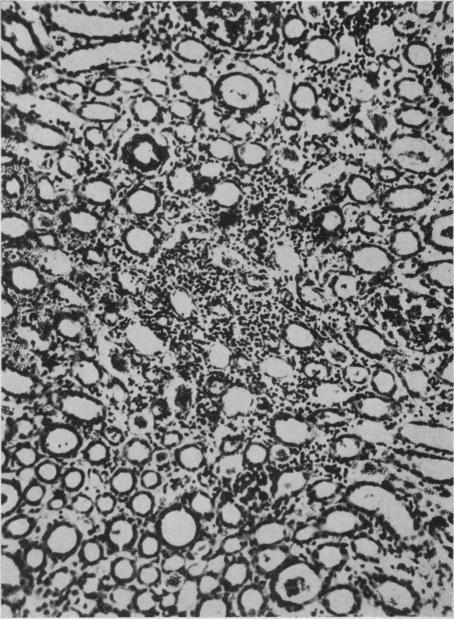

CARBON TETRACHLORIDE POISONING: REPORT OF CASES.

Cal West Med. 1944 Jul;61(1):16-20.